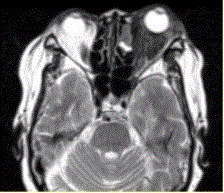

问题 患者女,64岁,左眼突出5年余。查体左眼球前突6mm,眼球运动自如,眼底无异常,下睑扪及边界不清、质软的肿块,视力正常,MR表现如下图。 诊为炎性假瘤,则此例患者的分型应为

选项 A.肿块型 B.弥漫炎症型 C.泪腺型 D.肌炎型 E.眼睑型 F.眼球型

答案 B